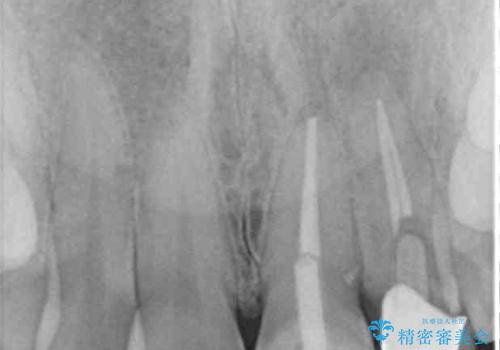

既にクラウンが装着されていた歯は歯根の先端に病変が認められたため、根管治療を行うこととしました。